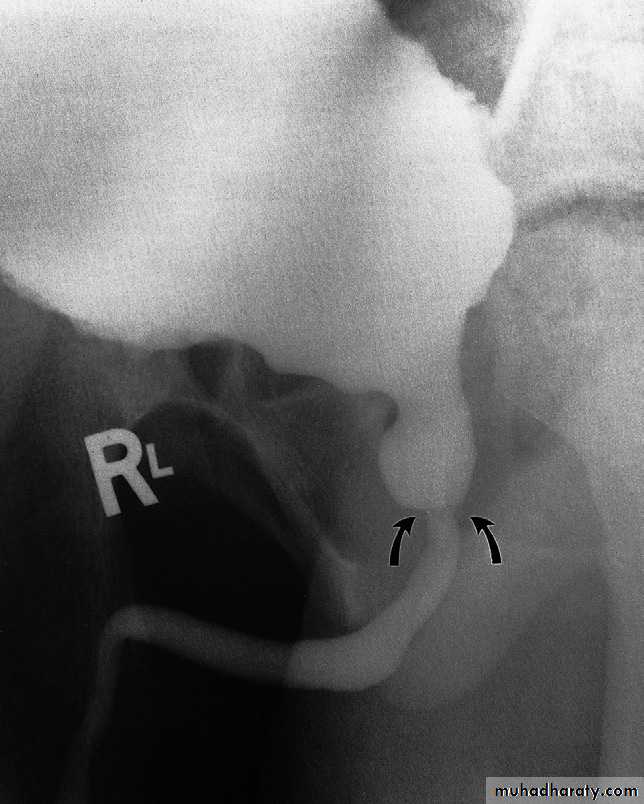

Voiding cystourethrogram (micturating cystogram) and videourodynamics

In voiding cystourethrography, the bladder is filled with iodinated contrast medium through a catheter and films are taken during voiding. The entire process is observed fluoroscopically to identify vesicoureteric reflux.The bladder and urethra can

be assessed during voiding

to demonstrate strictures or

urethral valves .

Videourodynamic examination

Combines voiding cystourethrography with bladder pressur measurements, which necessitate bladder and rectal pressure lines.It is indicated in the investigation

- Patient with incontinence to distinguish detrusor instability from sphincter weakness (stress incontinence).

-In elderly men with obstructive symptoms, to differentiate true

obstruction from bladder instability

- In patients with a neurogenic bladder.

Urethrography

The urethra is visualized during voiding cystourethrography.For full visualization of the male urethra, however, an ascending urethrogram with contrast medium injection via the external urethral meatus is necessary .The usual indications for the examination are:

- The identificationof urethral strictures

- To demonstrate extravasation from

the urethra or bladder neck

following trauma.